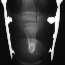

FOLLOW-UP: At 9 years of age the patient was noted to have an increased flexion contracture about the knee with radiographs demonstrating a recurrent valgus deformity. She subsequently underwent a repeat tibial derotational osteotomy with correction of the valgus deformity. Her postoperative course was uncomplicated. Currently she is 17 years old and ambulates well with the use of a custom below-knee PTB prosthesis with a carbon copy foot.